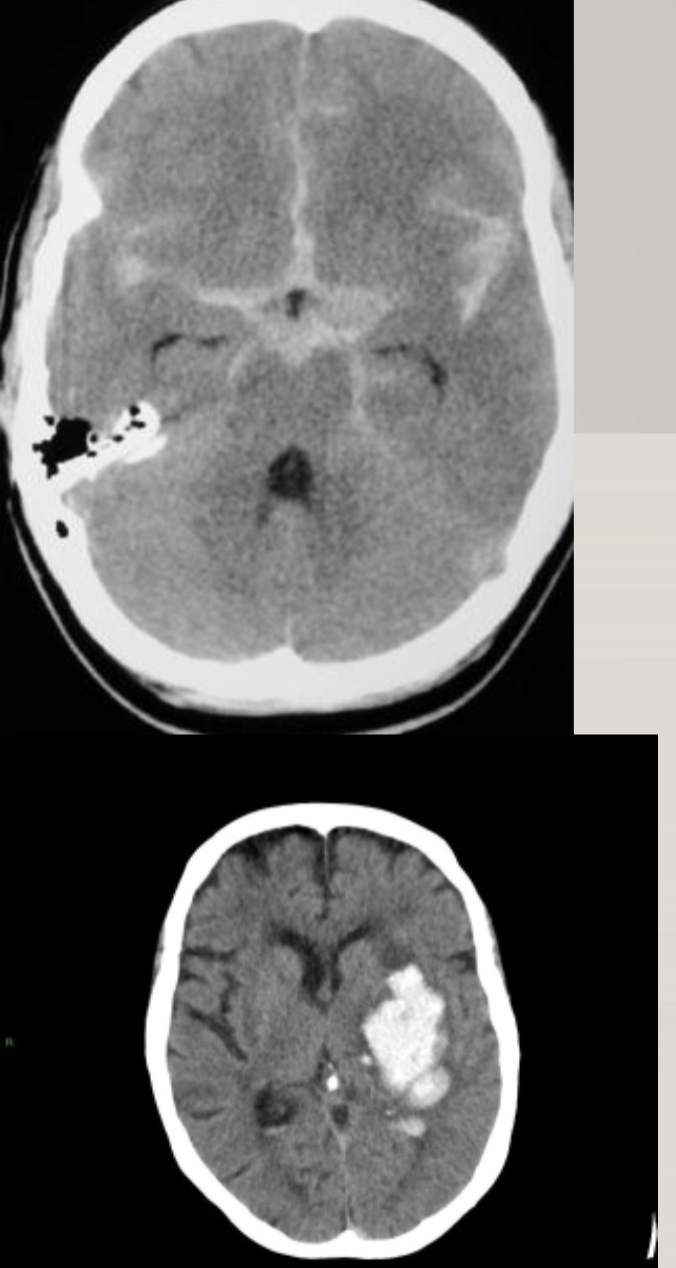

2 Types of hemorrhagic stroke

(star of death: aneurysm)